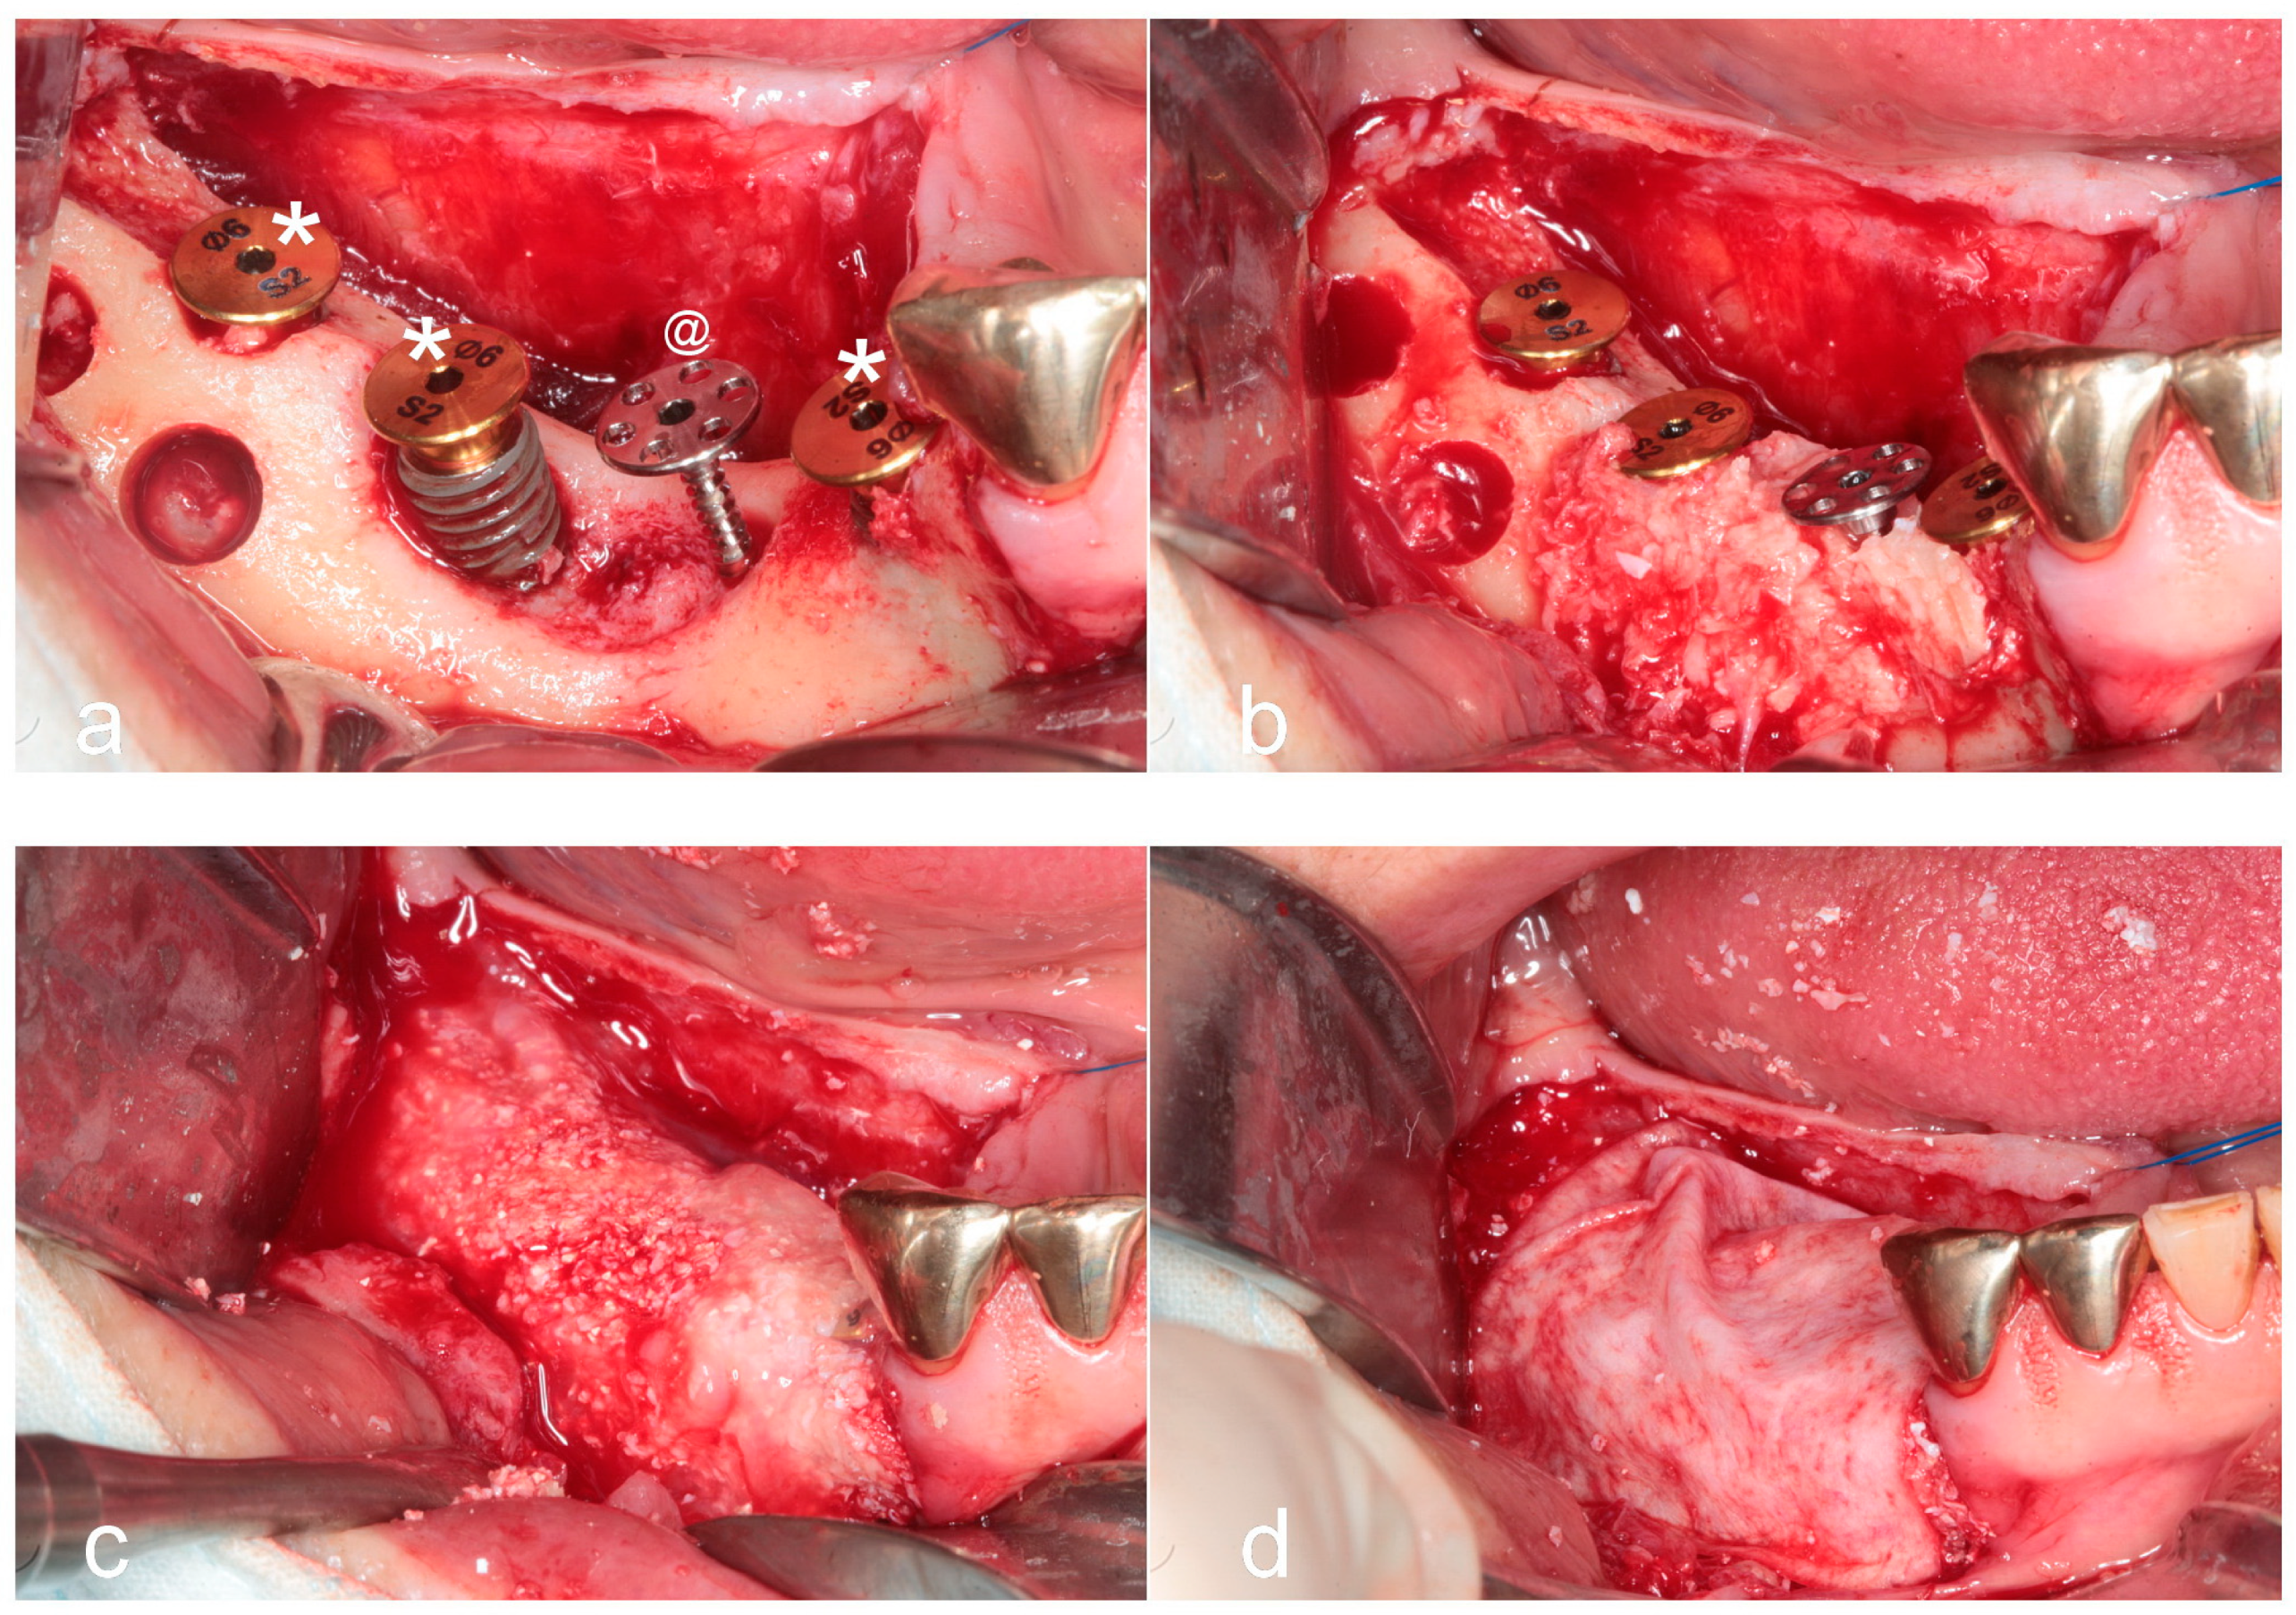

- Sohn, D.S. Reconstruction of three-dimensional alveolar ridge defects utilizing screws and implant abutments for the tent-pole grafting techniques. In Essential Techniques of Alveolar Bone Augmentation in Implant Dentistry, 2nd ed.; Tolstunov, L., Ed.; Wiley Blackwell: Hoboken, NJ, USA, 2023; pp. 404–418. [Google Scholar]

- Sohn, D.S.; Lui, A.; Choi, H. Utilization of tenting pole abutments for the reconstruction of severely resorbed alveolar bone: Technical considerations and case series reports. J. Clin. Med. 2024, 13, 1156. [Google Scholar] [CrossRef]